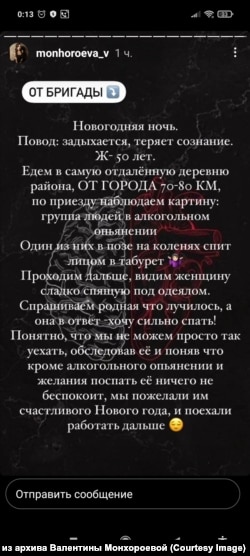

– В нашей БСМП такой опросник тоже не введен. Хотя и очень бы пригодился. Пока я слышала только об одном случае, напоминающем его применение – жительница одного из городов Иркутской области пожаловалась в сторис на то, что у нее поднялась температура, начался кашель, и она решила тут же звонить в скорую, а в диспетчерской ей якобы задали ряд вопросов и по итогу сказали, что она "недобрала баллов" для выезда экстренной бригады, посоветовали дозвониться до поликлиники, вызвать дежурного врача на дом.

Девушка написала, что дозвониться не смогла, пришлось, мол, в поликлинику самой идти, – рассказывает Валентина Монхороева диспетчер скорой помощи из Иркутска. – Мое мнение – так и должно быть: случай явно не экстренный, она успешно добралась сама до врача, лечение назначили. Среди указанных ею симптомов нет тех, что показаны к экстренной госпитализации. Так зачем же звонить сразу в скорую в таком случае?

По словам Валентины Монхороевой, после того как она у себя в соцсетях опубликовала пост о новом опроснике Минздрава, ее коллеги (также не получившие от начальства никаких рекомендаций на этот счет) стали массово присылать истории о ложных вызовах.